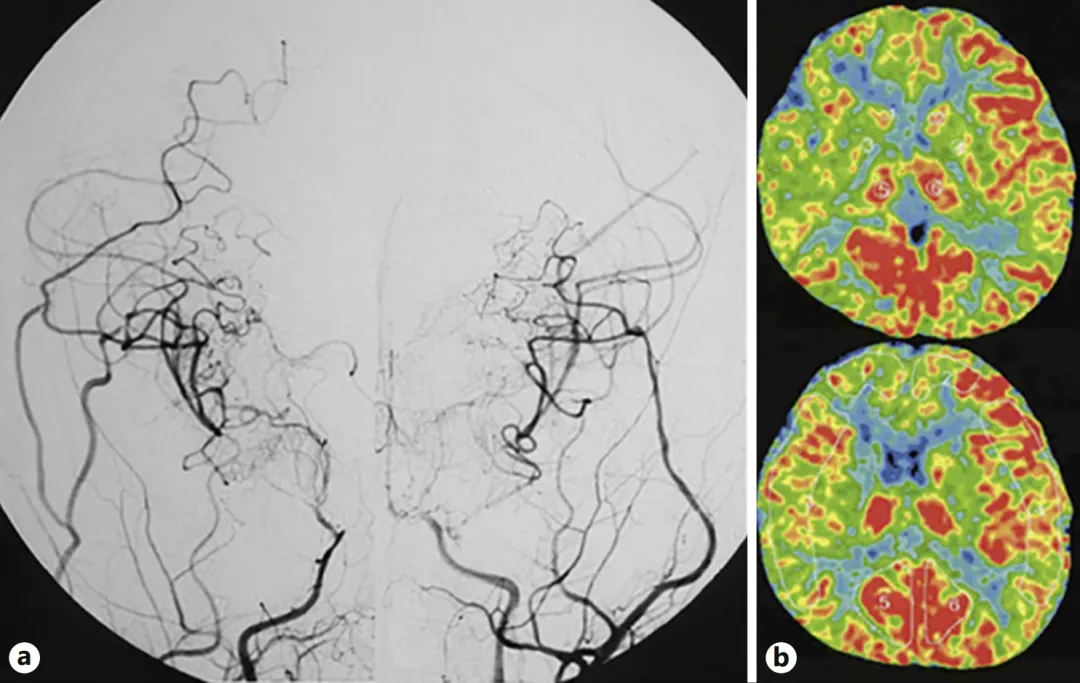

术后初期,患儿恢复情况非常理想:复查DSA(脑血管造影)显示,大脑侧支循环建立良好,基底节区的烟雾血管明显减少,脑血流也得到了显著改善。但医生并未因此放松警惕,术后仍让患儿继续服用药物预防血栓形成,并严格控制血压——这是预防术后高灌注及其他并发症的关键措施。

图a:第二次手术完成半年后,双侧颈内动脉血管造影显示,侧支血管网络发育良好,基底节区的烟雾血管已基本消退;

图b:双侧脑血流检查结果,也证实了脑组织供血情况得到了有效改善。